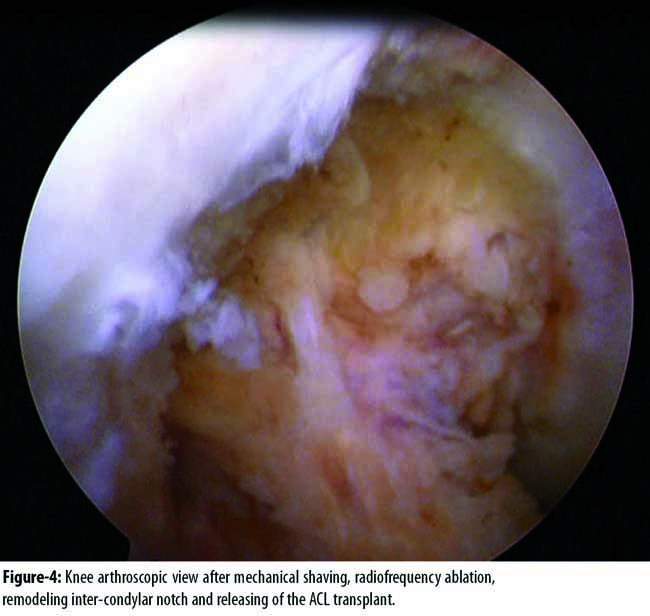

This was successfully treated by mechanical shaving, radiofrequency ablation, remodeling inter-condylar notch and releasing of the ACL graft (Figure-4)